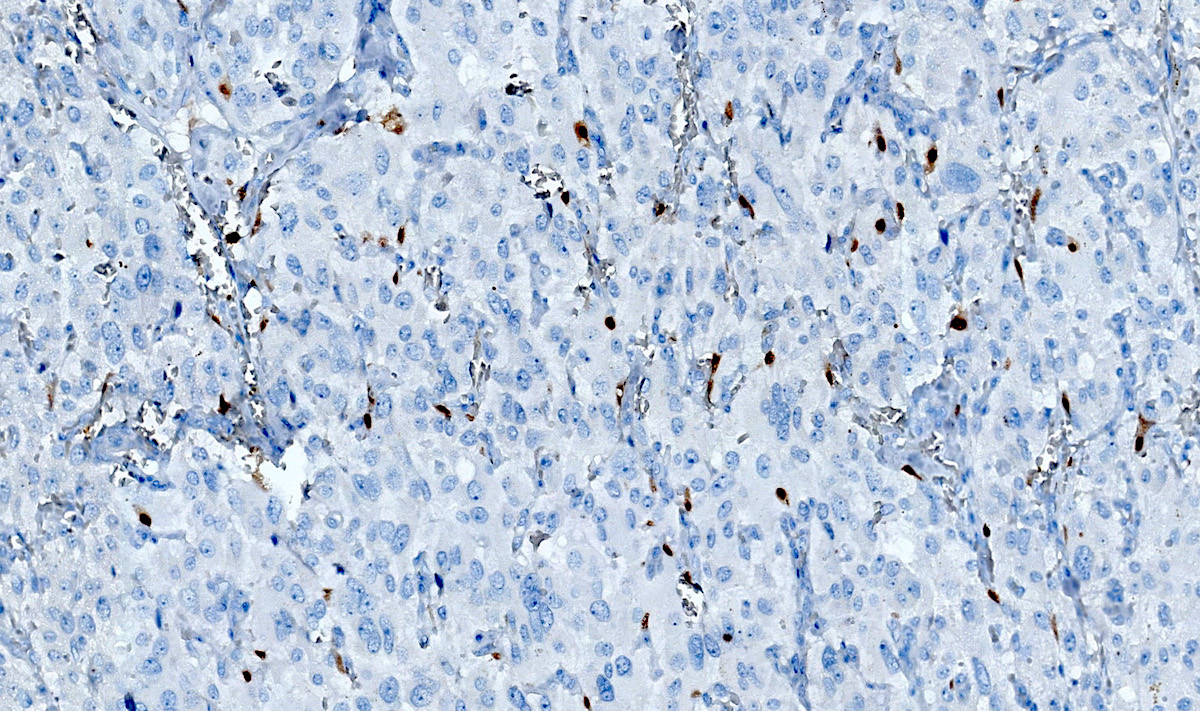

Microscopic (histologic) images

Contributed by Luvy Delfin, M.D. and Sylvia L. Asa, M.D., Ph.D.

Positive stains

- INSM1 (diffuse nuclear) (Am J Surg Pathol 2018;42:665)

- Chromogranin A (can be only focal or perinuclear dot-like golgi pattern)

- Synaptophysin (Histol Histopathol 1993;8:429)

- CD56 (Endocr Pathol 2002;13:149)

- S100 may be diffusely positive (J BUON 2018;23:1540)

- GATA3 (diffuse nuclear) (Hum Pathol 2020;103:72, Am J Surg Pathol 2014;38:13, J Clin Med 2018;7:280)

- Tyrosine hydroxylase (critical enzyme required for catecholamine synthesis; usually diffuse and strong in sympathetic paragangliomas, may be weak or focal in parasympathetic tumors) (Hum Pathol 2020;103:72)

- Dopamine beta hydroxylase and phenylethanolamine N methyltransferase (PNMT) (epinephrine producing tumors) (see Diagram below) (Neuroendocrinology 2015;101:289, J Clin Med 2018;7:280)

- Sustentacular cells: S100, GFAP and SOX10 (Hum Pathol 2020;103:72)

- Ectopic immunoexpression of hormones: serotonin, ACTH, CRH, VIP, leu enkephalin substance P, gastrin, somatostatin, vasopressin, MSH and calcitonin (Arch Endocrinol Metab 2017;61:291, J Clin Endocrinol Metab 2021;106:598, Endocr Pract 2014;20:e145, Ann Intern Med 1979;91:208)

- IHC surrogate markers for germline mutations:

- SDHB or SDHA expression loss: germline SDHx mutations (Lancet Oncol 2009;10:764)

- FH expression loss: germline FH mutation (HLRCC) (Hum Pathol 2018;71:47)

- Carbonic anhydrase IX (CAIX) expression: 80% of VHL mutation (Mod Pathol 2020;33:57)

- Inhibin alpha: any hypoxic pathway disease (SDHx, VHL, etc.) (Am J Surg Pathol 2021;45:1264)

- Reticulin highlights the nesting pattern (Int J Gynecol Pathol 1991;10:203, Exp Toxicol Pathol 2013;65:631)

Contributed by Luvy Delfin, M.D. and Sylvia L. Asa, M.D., Ph.D.